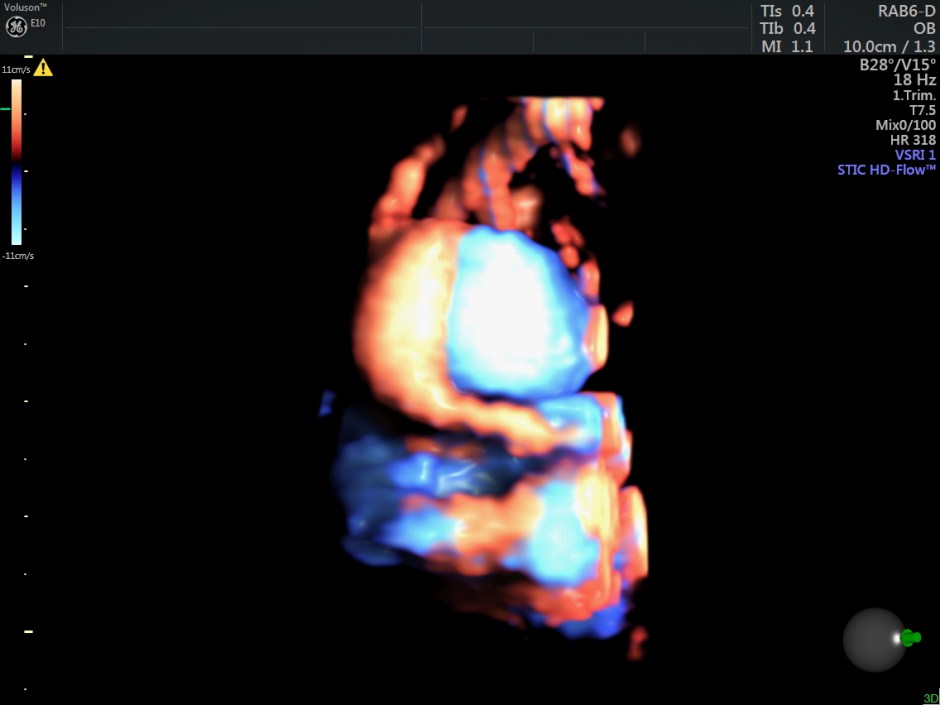

Reconstructed images show the feeding vessel and a vessel leaving the vascular structure.

STIC HIGH DEFINITION FLOW reconstruction images also show a feeding vessel and a vessel leaving the vascular structure,